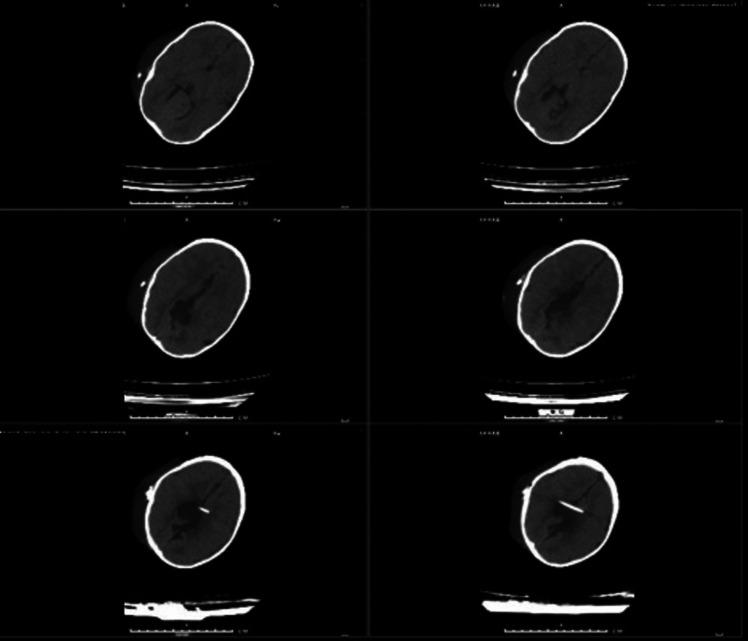

Post infective hydrocephalus (PIH) is a type of hydrocephalus which occurs after an infection of the brain or cerebrospinal fluid (CSF). Treatment of PIH requires temporary measures such as external ventricular drain (EVD) and ventriculosubgaleal shunt (VSGS) until CSF becomes clear and ready to implement VP shunt. Limited research has been done to explore the tradeoff between these approaches particularly in pediatric PIH patients. Our study compares the complications, mortality rates, and the cost of used resources of both procedures.

A prospective study was conducted for 18 months in which we compared between VSGS and EVD for management of PIH involving 42 randomized cases with 21 patients in group A operated by VSGS and 21 patients in group B operated by EVD.

Our results show a statistically significant difference between both groups in the duration of implementation of VSGS/EVD until resolution of infection occurs. Additionally, a higher rate of pediatric intensive care unit (PICU) admission and a longer length of hospital stay (LOS) were recorded among the EVD group. No statistically significant difference between the number of complications that happened in both despite variations in their forms. Moreover, both groups showed nearly similar mortality rates.

There is no significant difference in the rate of complications between VSGS and EVD for PIH. Based on that, VSGS emerges as a favorable and cost-effective option for the management of PIH which leads to less economic burden on patients and the country's health resources, especially in developing countries.